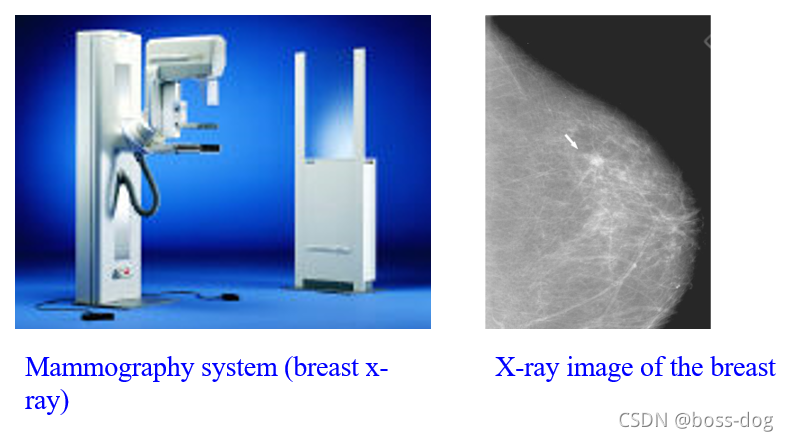

Mammography(乳腺癌钼靶成像)

分辨率很高。

A:数字化钼靶片(digital mammography),是透射图像,相当于整个乳腺的每一层的组织都把它重叠到一张图。

B:层析X射线照相组合(Tomosynthesis),通过不同的角度得到透视图,从而重建出断面的图像,看的更清楚,就可以去掉那些不同高度的图像组织的重叠。